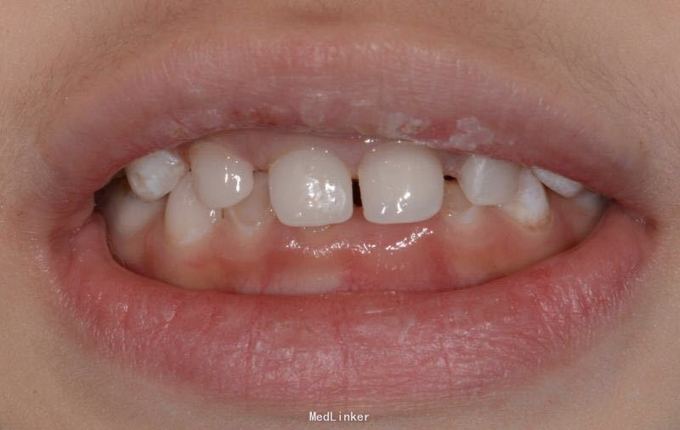

儿童6岁乳上前牙只剩牙根,唇侧牙龈有瘘管口半月,特来就诊

A1 B1 残根,可探及根管内,有黑褐色腐质物,扣(-),探(-),无松动,唇侧牙龈微红肿,各有一个瘘管口,压有浓液渗出物,A2 B2残根,呈黄褐色扣(-),探(-),无松动。

A1 B1残根,根尖炎。 常规根管治疗,树脂充填,抛光 A2 B2残根,常规去腐,备洞,树脂充填,抛光

乳牙功能恢复对发音,面部肌肉骨骼生长,儿童自信心的增长都有帮助